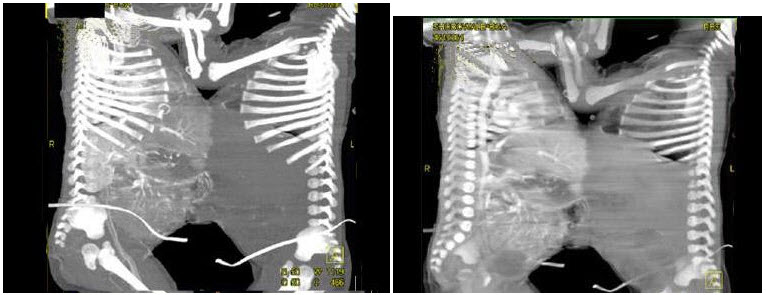

25、单项选择题

根据所提供的图像,这两个连体双胎的最可能的诊断是()